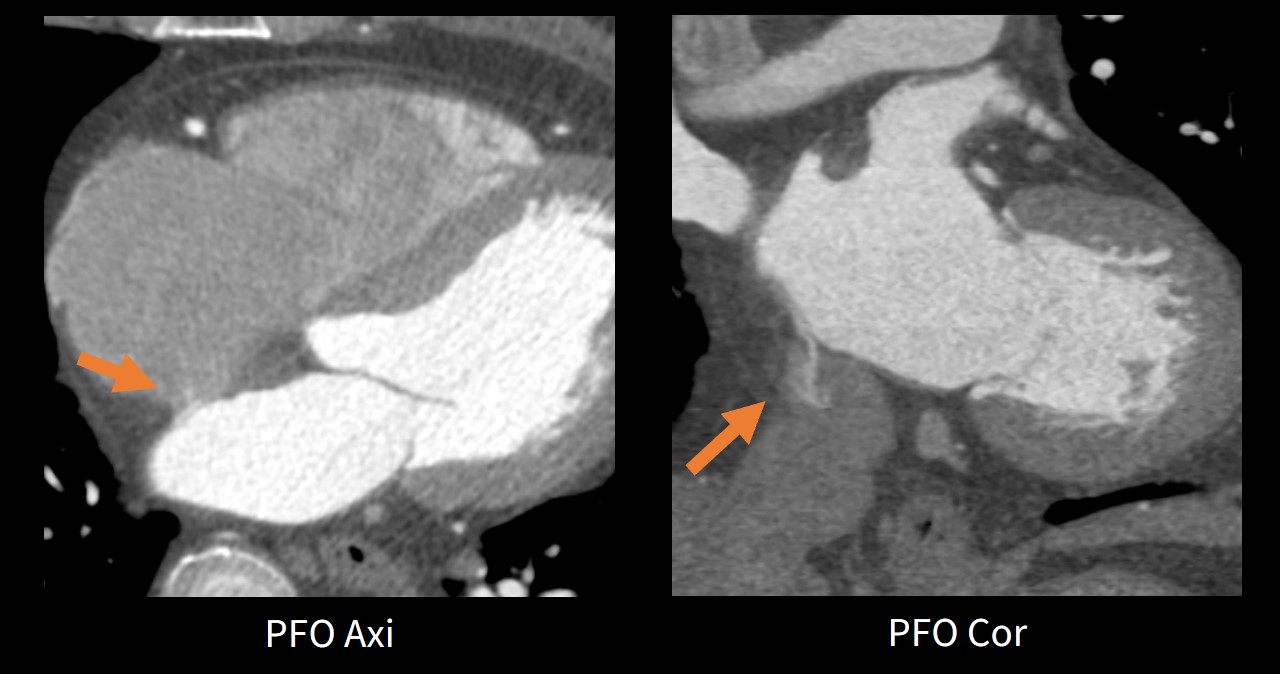

【PFOの検出】

当院の対象患者はほとんどが脳卒中の既往歴がある。特に問題となるのが脳梗塞の原因となる心房細動症例の左心耳内血栓やPatent Foramen Ovale (PFO)などの心臓内構造物である。

SSF20_ookawara07.jpg

Fig4.SSF2.0症例